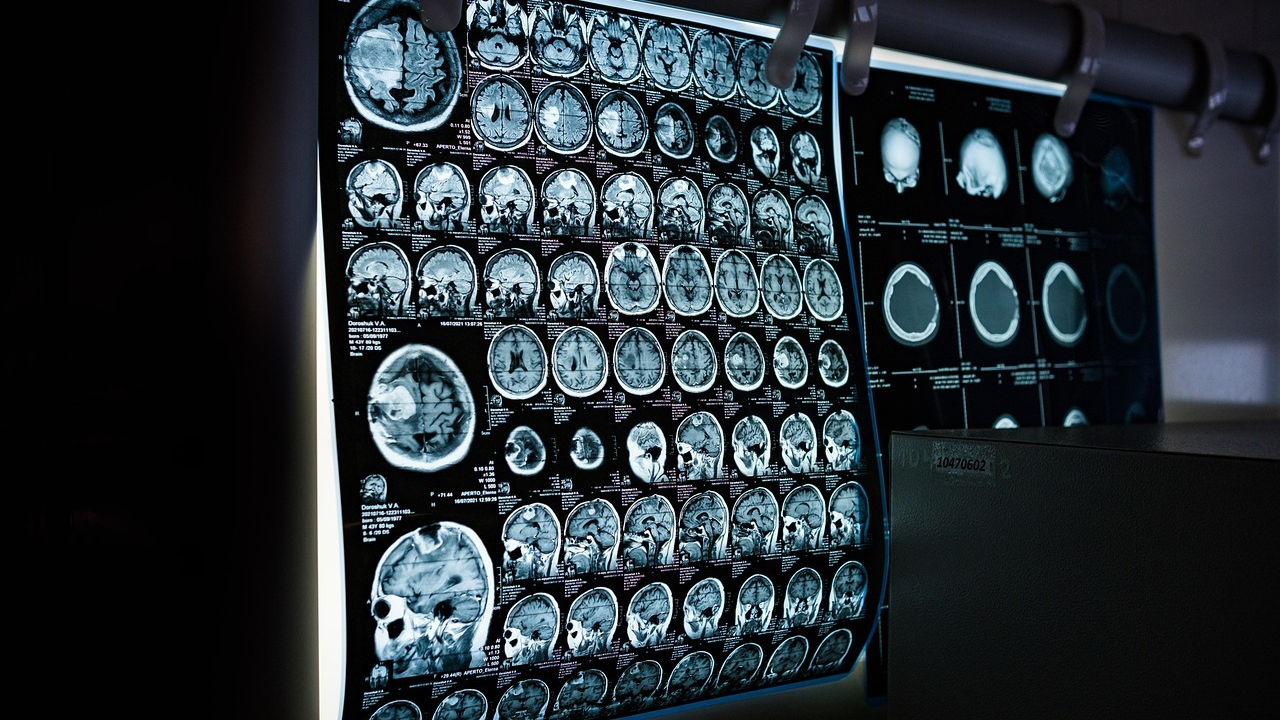

Osobe oboljele od multiple skleroze u Hrvatskoj će od sada imati učinkovitije liječenje

Osobe s multiplom sklerozom u Hrvatskoj od ovoga mjeseca imaju mogućnost liječenja sa svom dostupnom terapijom odmah nakon postavljanja dijagnoze, što znači da će manji broj oboljelih razviti invaliditet, istaknuli su u ponedjeljak predstavnici neurološke struke i pacijenata.